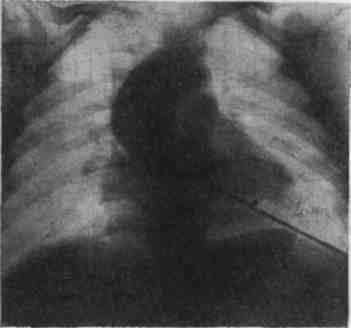

При рентгенологическом исследовании из-за увеличения левого желудочка сердце приобретает так наз. аортальную конфигурацию, напоминая форму башмака (рис.2). Левая граница сердца смещена иногда до передней подмышечной линии.

Рис. 2. Клапанный стеноз аорты: "талия" сердца выражена, левый желудочек увеличен.

Сердечная "талия" выражена достаточно хорошо; левое предсердие и ствол легочной артерии расширяются лишь при недостаточности левого желудочка. В левом косом положении виден увеличенный массивный левый желудочек. Уже по обзорной рентгенограмме можно судить о расширении восходящей аорты. При рентгенокимографии определяются резко выраженные увеличенные, часто деформированные из-за миокардиодистрофии зубцы левого желудочка. В то же время пульсация восходящего отдела аорты бывает выражена слабо. Выраженной гипертензии малого круга кровообращения не развивается, поэтому легочный рисунок, как правило, не изменен: легочная артерия и ее ветви не расширены. При зондировании правых полостей сердца при этом пороке характерных изменений не выявляется.